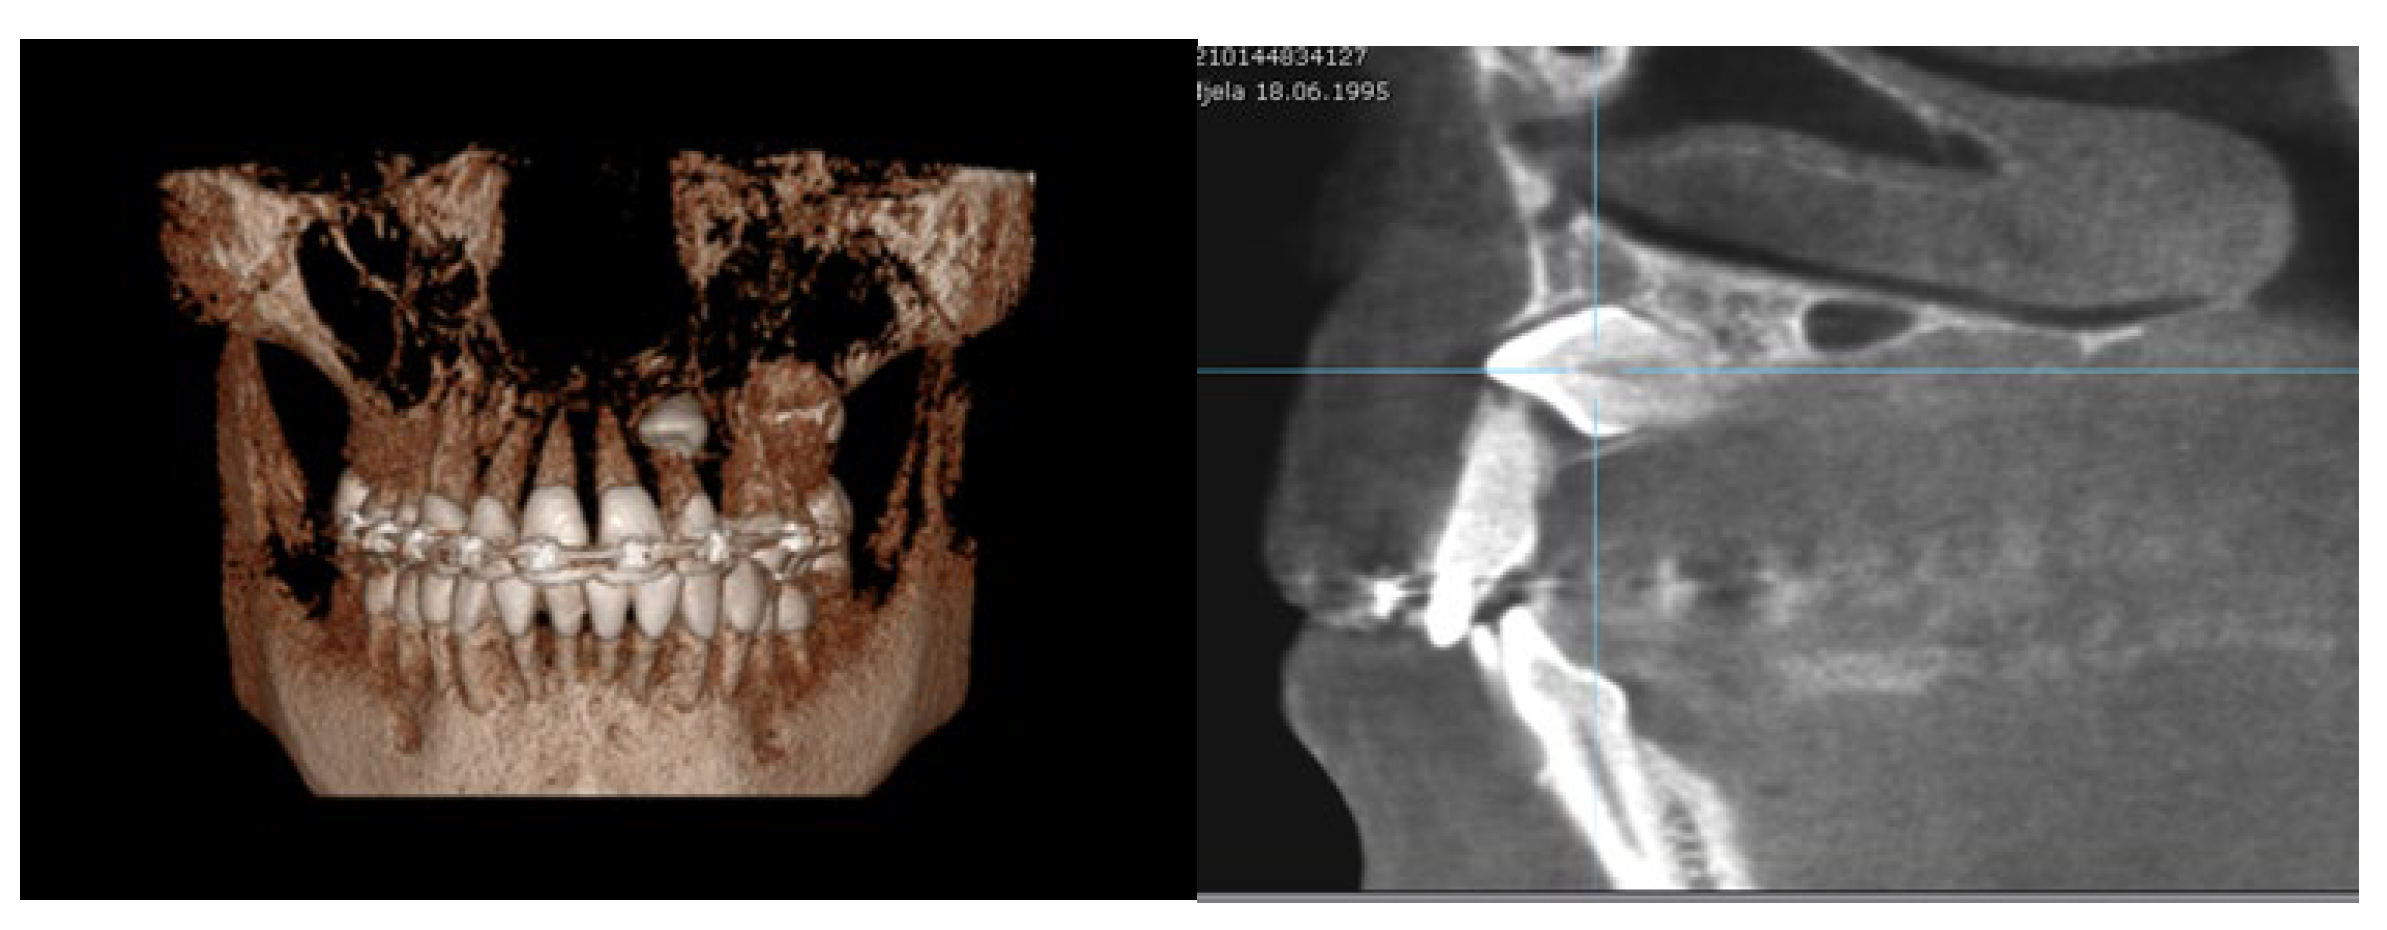

- Angle between the longitudinal axis of the impacted maxillary canine and the maxillary arch midline (measured on CBCT images in the coronal plan) (Figure 3a);

Figure 3. (a) Maxillary impacted canine angulation to the midline (measured on CBCT images in the coronal plan); (b) maxillary impacted canine angulation to the occlusal line and the distance canine cusp to occlusal line (measured on CBCT images in the sagittal plane).Figure 3. (a) Maxillary impacted canine angulation to the midline (measured on CBCT images in the coronal plan); (b) maxillary impacted canine angulation to the occlusal line and the distance canine cusp to occlusal line (measured on CBCT images in the sagittal plane).

Angle between the longitudinal axis of the impacted maxillary canine and the occlusal line (measured on CBCT images in the sagittal plane) (Figure 3b); - (9)

In the group with RR, the average angle between the impacted canines and midline was 46.7°, and the average angle between the impacted canines and the adjacent lateral/central incisors was 43.1°/40.3°. The average angle between the canine and occlusal line was 43.6°, whereas the average angle in the group with no resorptions was 55.8° (Table 3). Based on the clinical findings in the group of subjects with RR on the incisors, the angulation of the impacted canine to the midline and angulation to the incisor were found to have significantly higher values than in the group of subjects with no resorption. On the other hand, the angulation of the impacted canine to the occlusal line was found to be lower than in subjects with no resorption, and it was statistically confirmed (Figure 2).

There is a significant statistical correlation between the severity of RR on incisors and the angulation of the impacted canine to the incisor, affected by the resorption and angulation of the canine to the midline. More precisely, higher values of these angulations cause severe forms of RR. Regarding the impacted maxillary canine angulation to the occlusal line, no statistical significance with incisor RR was shown.